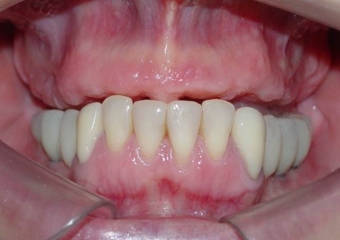

Imagens iniciais

Sorriso inicial